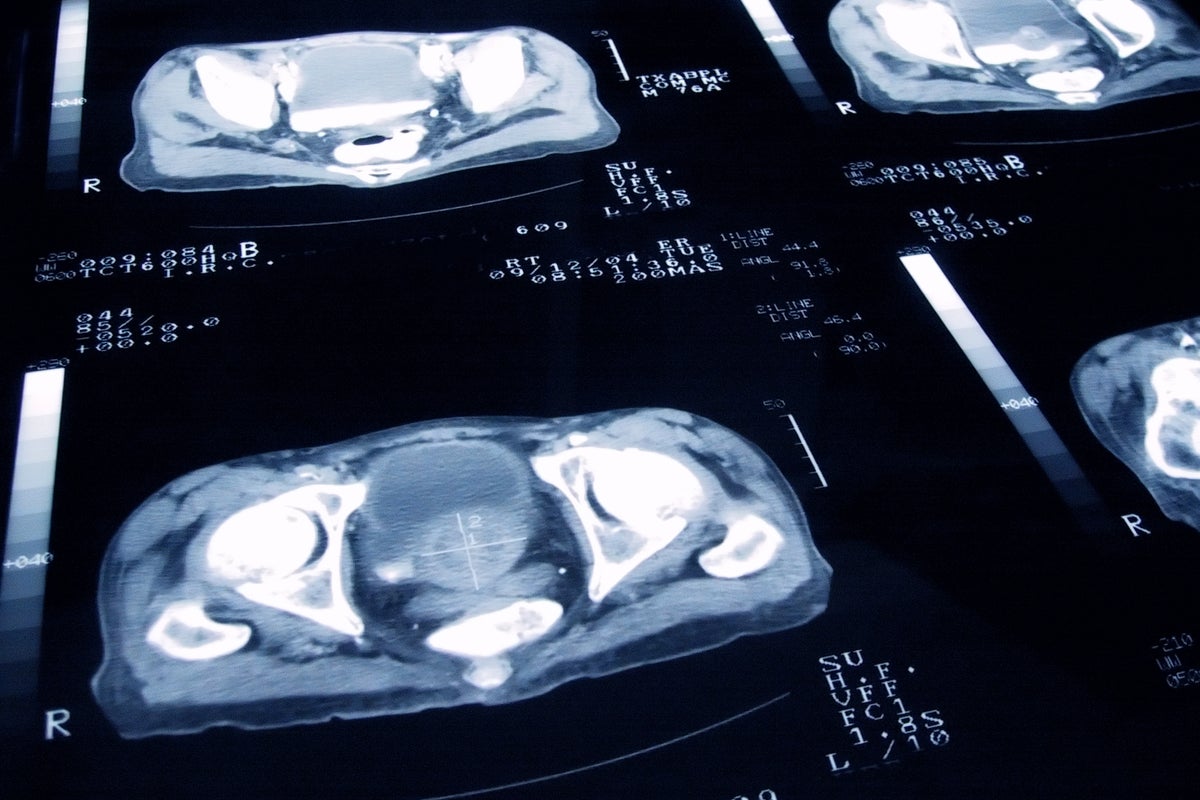

새로운 전립선암 검사가 공격적인 형태의 전립선암 발견을 개선하는 것으로 밝혀졌습니다. 이 검사는 전립선암 진단의 정확성을 높이고 조기 치료를 가능하게 하여 환자들에게 더 나은 예후를 제공할 수 있습니다....